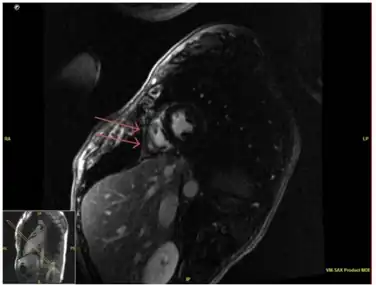

Pericardial enhancement of right ventricular free wall on cardiac MRI consistent with acute pericarditis.